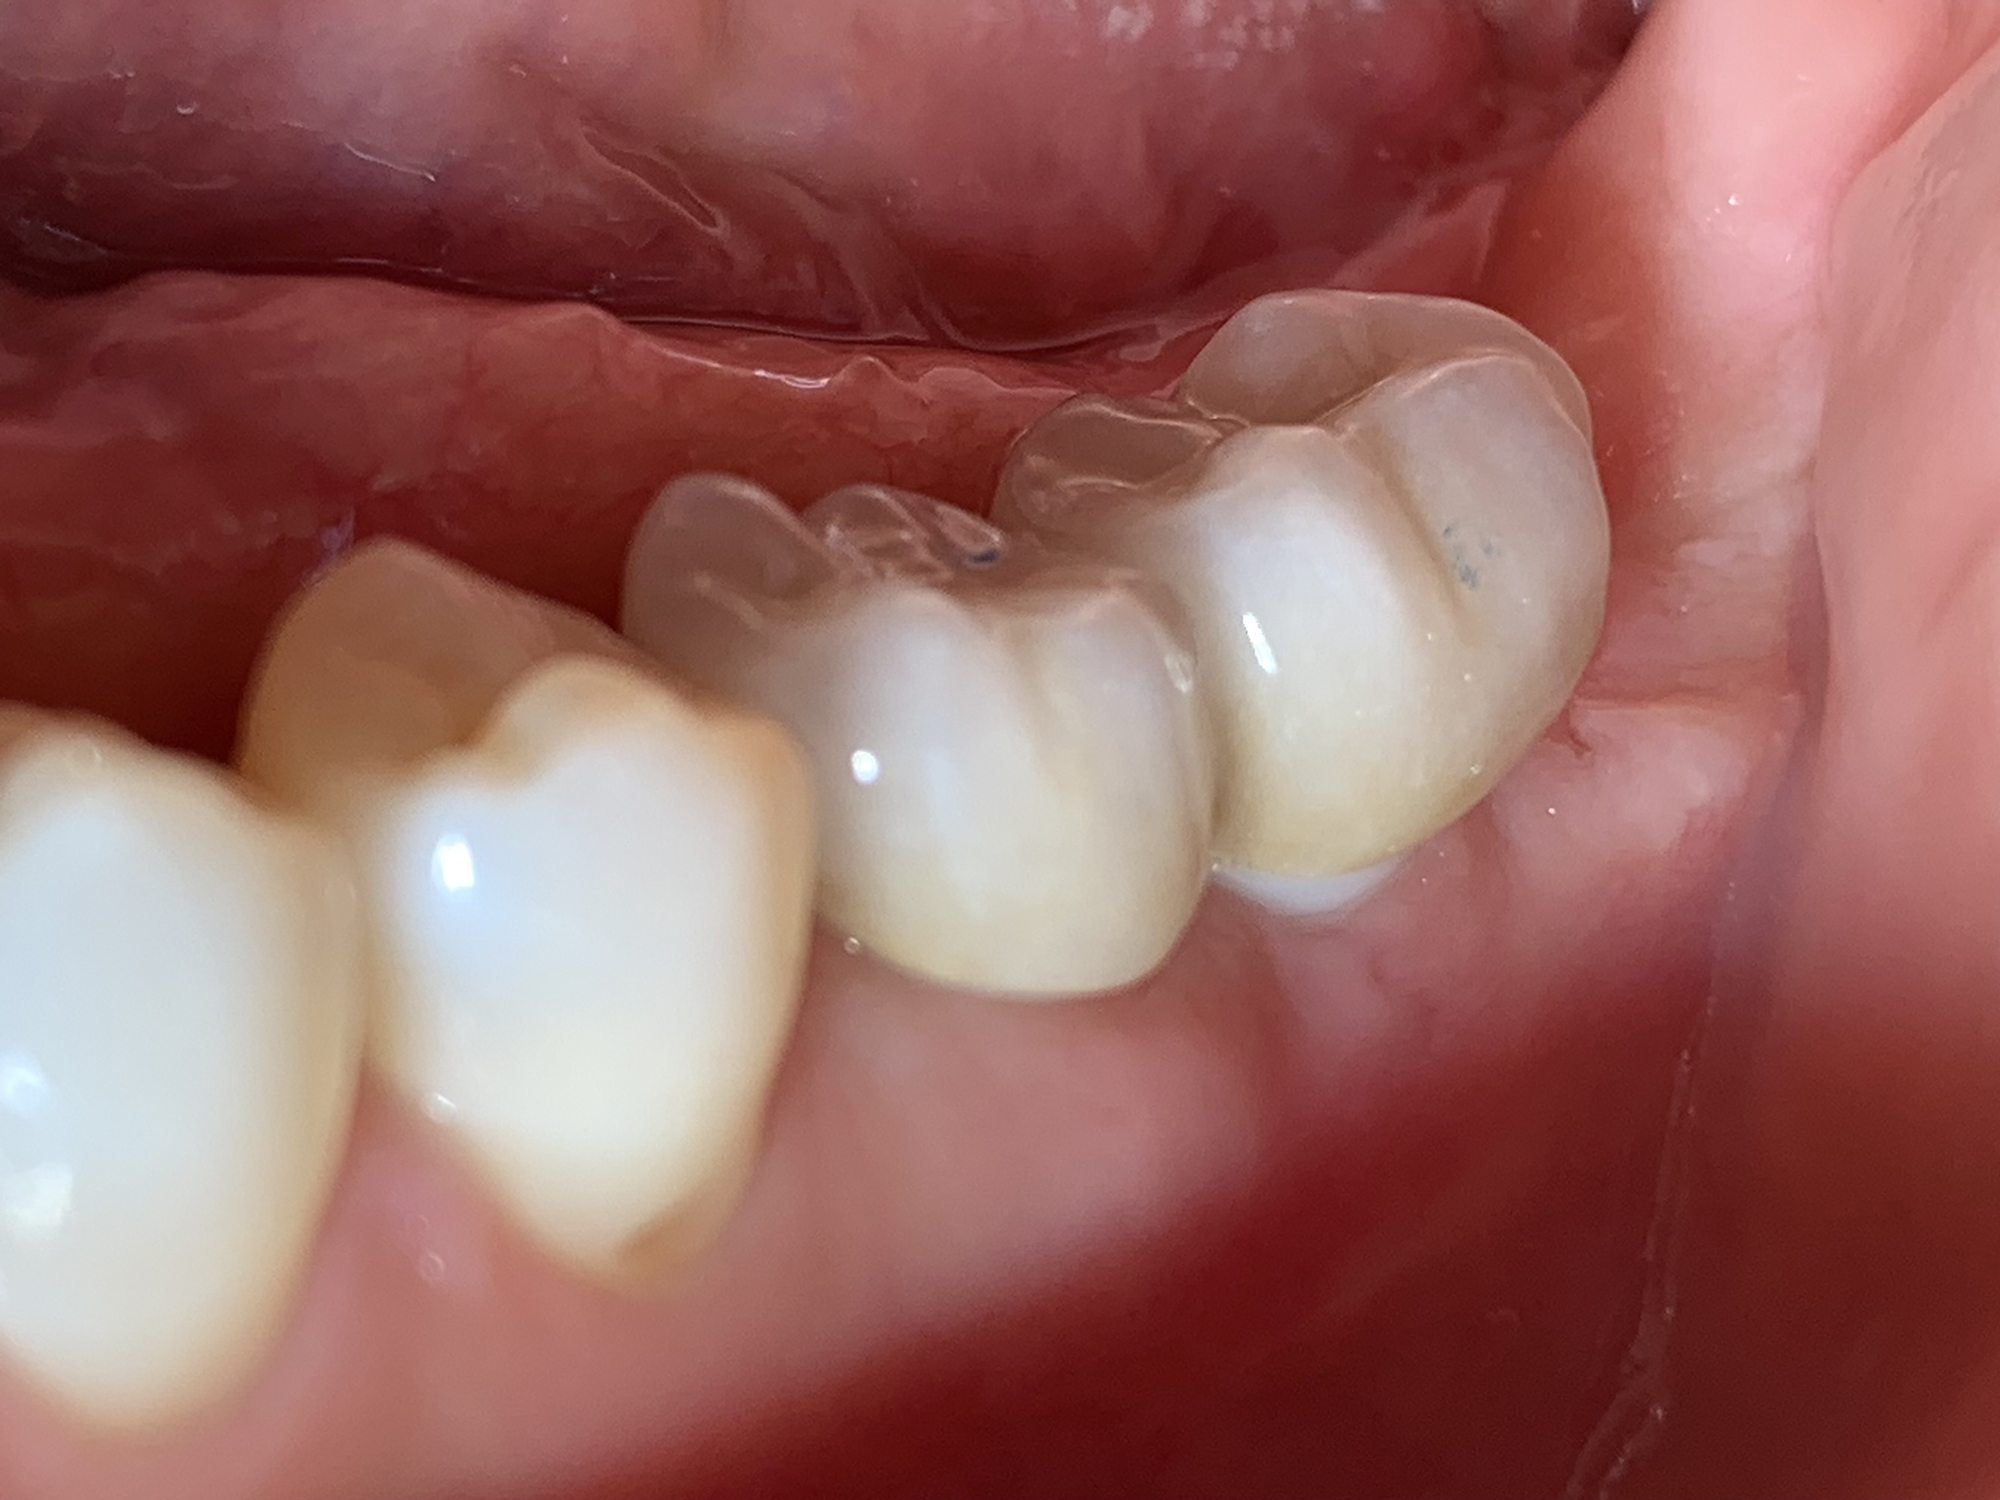

Keramikimplantate

Wir setzen auf hochwertige Keramikimplantate von Swiss Dental Solutions. Diese sind metallfrei, ästhetisch, verträglich und lassen sich oft in nur einer Sitzung einsetzen – für ein natürlich schönes Lächeln.

• Die helle Farbe im Vergleich zu den schwarzgrauen Titanimplantaten garantiert ein natürliches Lächeln und eine herausragende Ästhetik

• Auch in Sachen Stabilität sind Keramik-Implantate aus der Hochleistungskeramik Zirkoniumoxid in der Zwischenzeit den Titanimplantaten überlegen: bei gleichem Durchmesser weisen sie eine höhere Bruchsicherheit auf